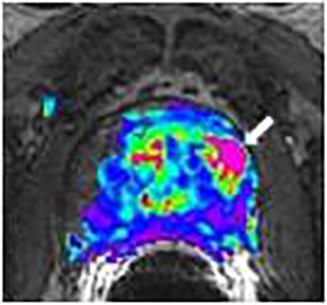

Figure 1 is a 48 year old male with a PSA of 5.23 ng/ml and biopsy proven prostate carcinoma of Gleason score 10 (5.5).

Diffusion weighted imaging (DWI): DWI is a technique involving the exchange of water molecules (diffusion) between prostate tissue compartments Figure 1c. Diffusion rates vary between normal and pathologic tissue. With DWI, the MRI machine is set to detect small restrictions in the free movement of water within the prostate gland and provide information about cellular crowding, seen in areas of increased cell turnover.